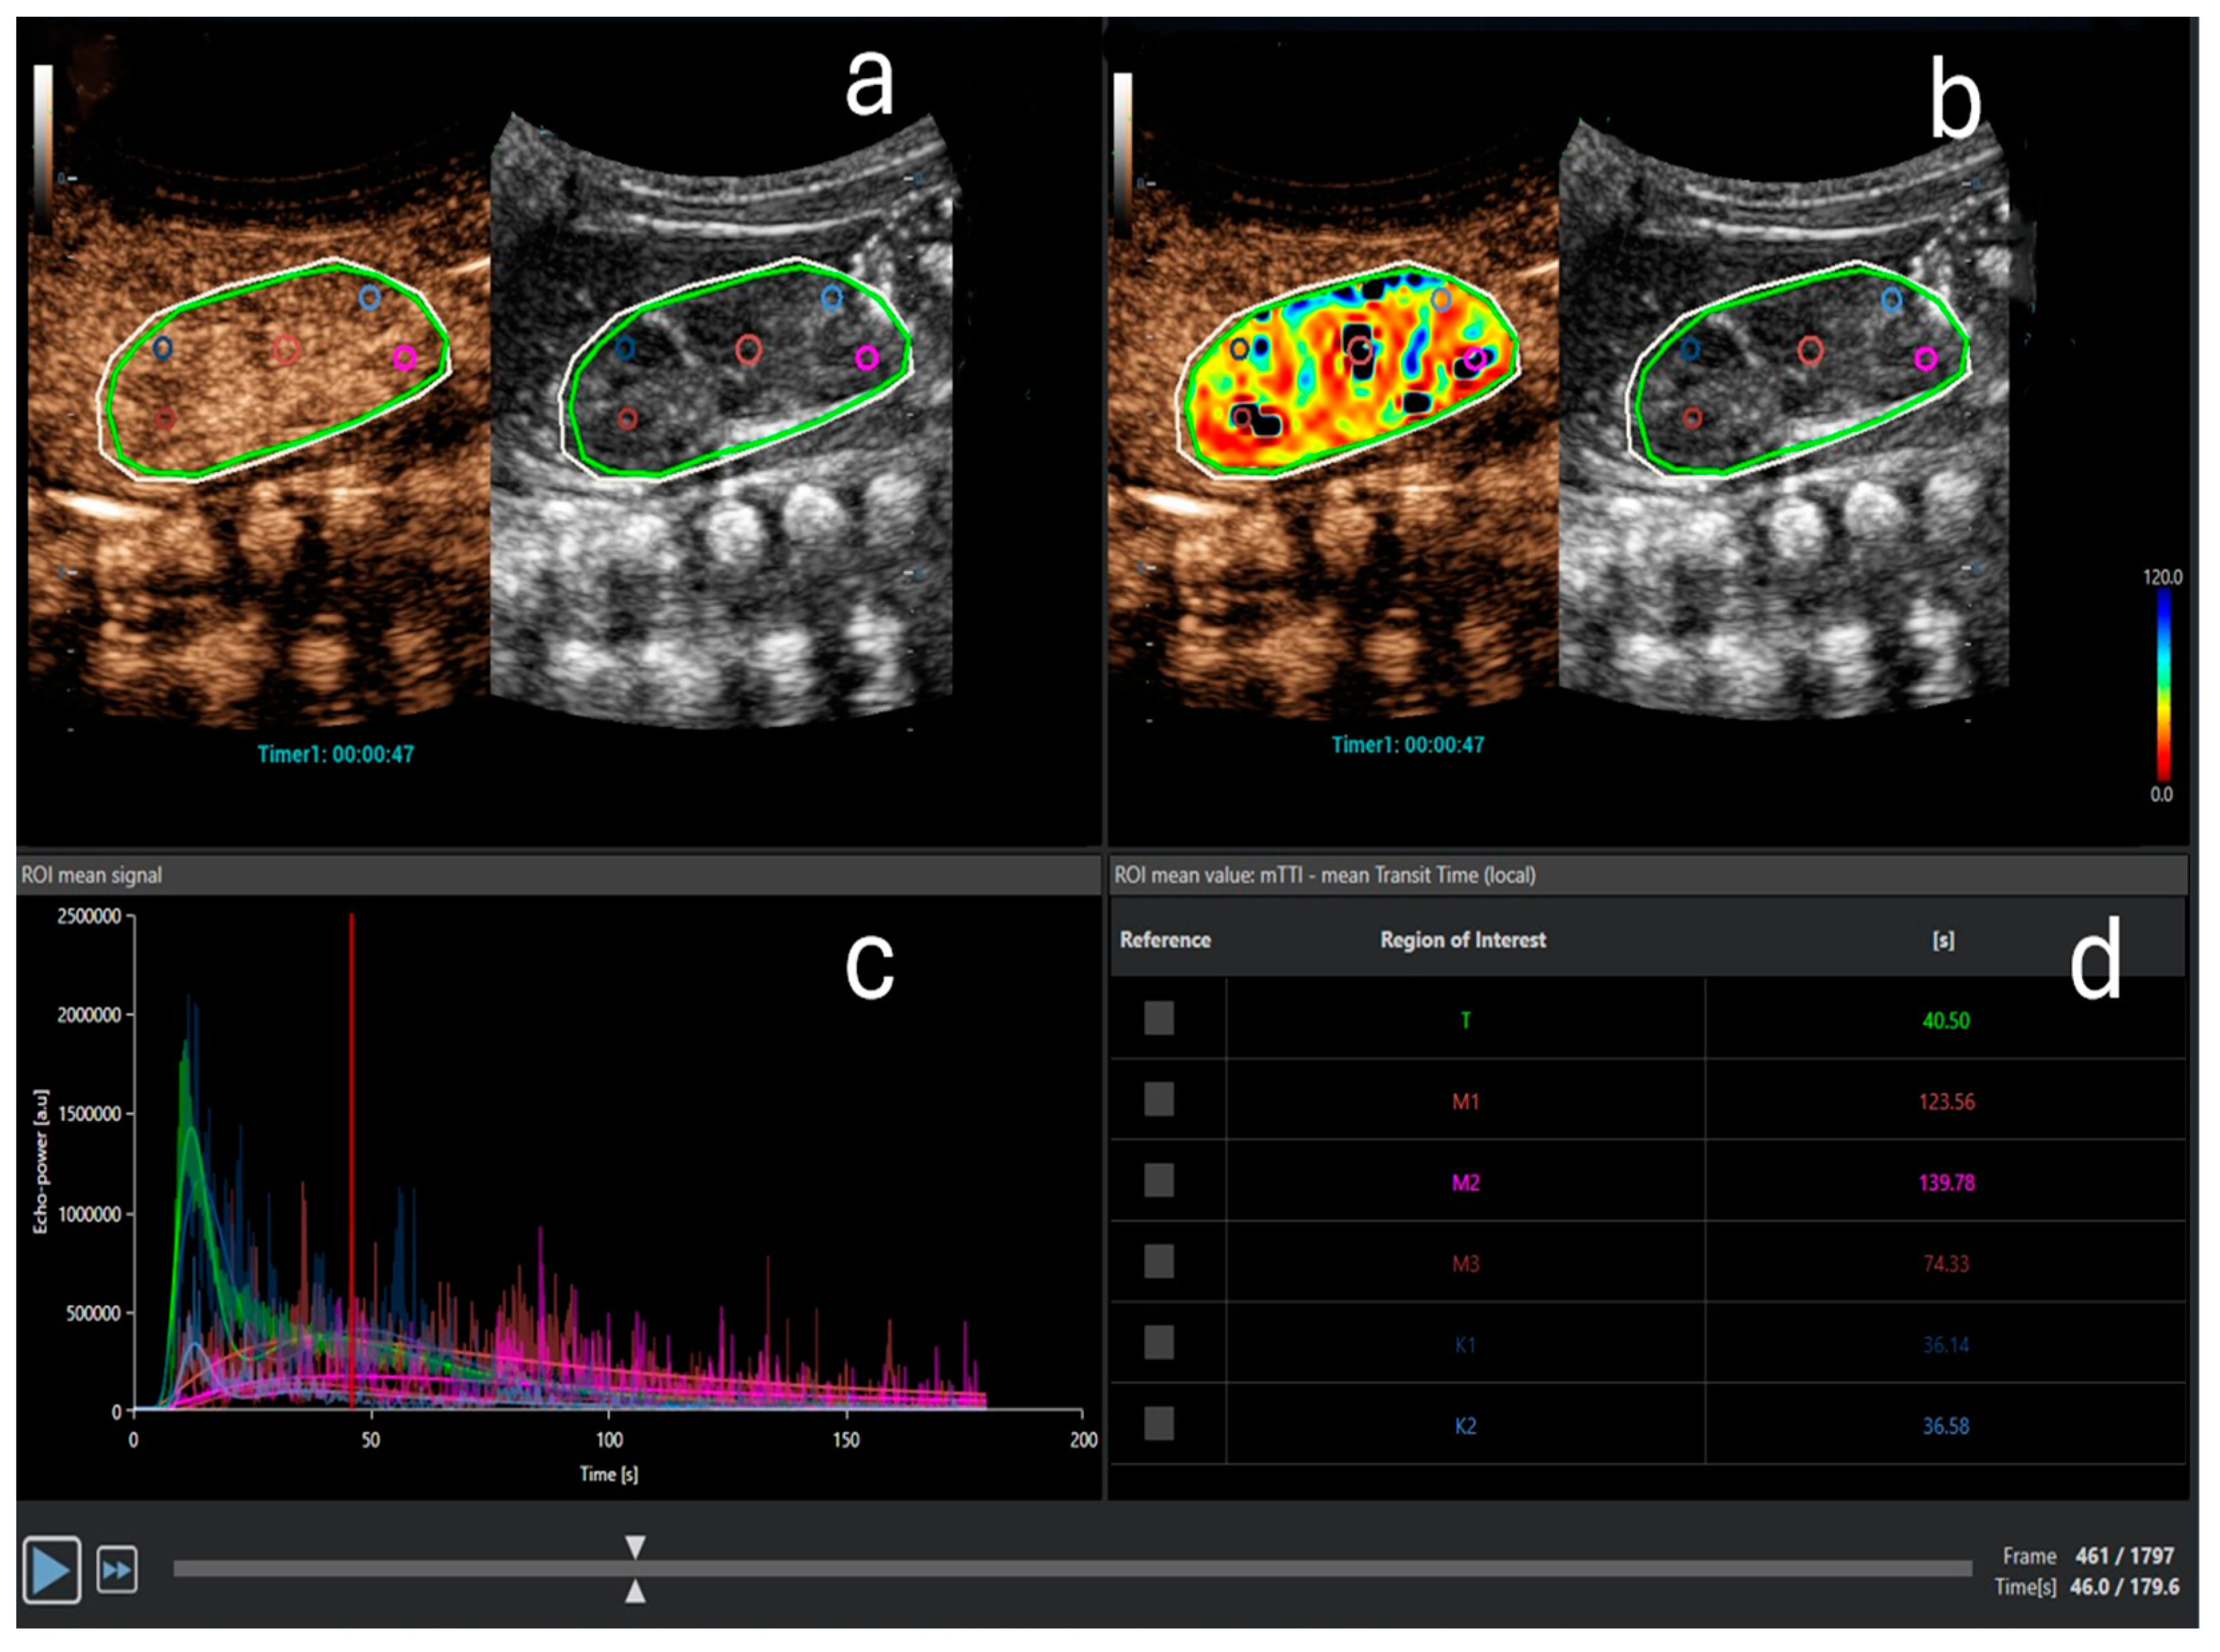

5. Contrast-Enhanced Ultrasound (CEUS) in AKI

- Cao, W.; Cui, S.; Yang, L.; Wu, C.; Liu, J.; Yang, F.; Liu, Y.; Bin, J.; Hou, F.F. Contrast-Enhanced Ultrasound for Assessing Renal Perfusion Impairment and Predicting Acute Kidney Injury to Chronic Kidney Disease Progression. Antioxid. Redox Signal. 2017, 27, 1397–1411. [Google Scholar] [CrossRef]

- Wang, X.-Y.; Pang, Y.-P.; Jiang, T.; Wang, S.; Li, J.-T.; Shi, B.-M.; Yu, C. Value of Early Diagnosis of Sepsis Complicated with Acute Kidney Injury by Renal Contrast-Enhanced Ultrasound. World J. Clin. Cases 2019, 7, 3934–3944. [Google Scholar] [CrossRef] [PubMed]

- Watchorn, J.; Huang, D.; Bramham, K.; Hutchings, S. Decreased Renal Cortical Perfusion, Independent of Changes in Renal Blood Flow and Sublingual Microcirculatory Impairment, Is Associated with the Severity of Acute Kidney Injury in Patients with Septic Shock. Crit. Care 2022, 26, 261. [Google Scholar] [CrossRef]

- Li, Y.; Chen, L.; Feng, L.; Li, M. Contrast-Enhanced Ultrasonography for Acute Kidney Injury: A Systematic Review and Meta-Analysis. Ultrasound Med. Biol. 2023, 49, 1930–1939. [Google Scholar] [CrossRef] [PubMed]

- Song, Y.; Mei, J.; Xu, D.; Ma, Y. Evaluation of Contrast-Enhanced Ultrasound in Diagnosis of Acute Kidney Injury of Patients in Intensive Care Unit. Int. J. Gen. Med. 2023, 16, 2229–2236. [Google Scholar] [CrossRef]

- Zhang, W.; Yi, H.; Cai, B.; He, Y.; Huang, S.; Zhang, Y. Feasibility of Contrast-Enhanced Ultrasonography (CEUS) in Evaluating Renal Microvascular Perfusion in Pediatric Patients. BMC Med. Imaging 2022, 22, 194. [Google Scholar] [CrossRef]

- Tang, M.-X.; Mulvana, H.; Gauthier, T.; Lim, A.K.P.; Cosgrove, D.O.; Eckersley, R.J.; Stride, E. Quantitative Contrast-Enhanced Ultrasound Imaging: A Review of Sources of Variability. Interface Focus. 2011, 1, 520–539. [Google Scholar] [CrossRef] [PubMed]

- Almushayt, S.J.; Pham, A.; Phillips, B.E.; Williams, J.P.; Taal, M.W.; Selby, N.M. Repeatability of Contrast-Enhanced Ultrasound to Determine Renal Cortical Perfusion. Diagnostics 2022, 12, 1293. [Google Scholar] [CrossRef]